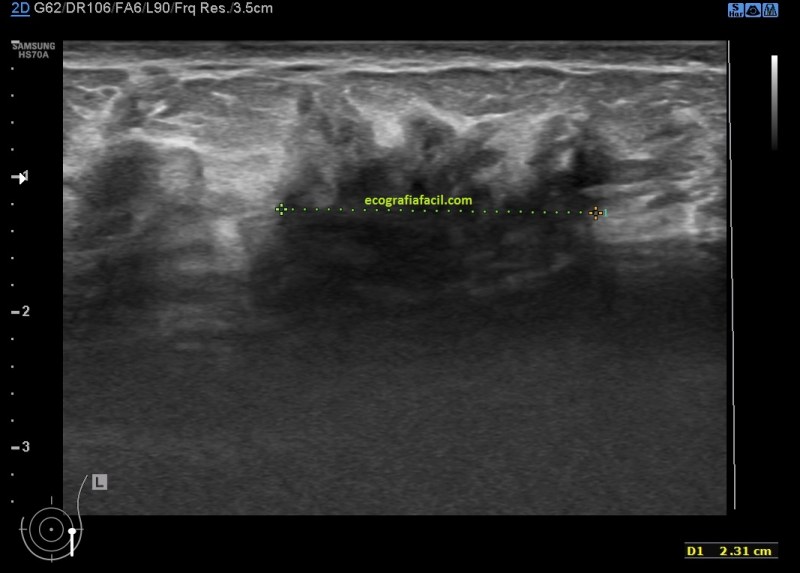

El estudio ecográfico mostró:

1. Mamas de predominio fibroso.

2. Acúmulos de tejido asímétricos de tejido fibroso de aspecto altamente denso e hipoecogénico de contorno mal definido en ambas mamas con ausencia de doppler color.

3. Mastopatía Diabética

4. Mastopatía Diabética

5. Mastopatía Diabética

6. Mastopatía Diabética. Doppler Color.

De la imagen 3 a la 6 tienes el aspecto semiolólogico normal de una mama diagnosticada de Mastopatía Diabética.